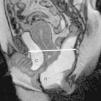

Prolapsos uterino y vaginal. La cúpula vaginal y el útero, debilitados o diseccionados sus soportes ligamentosos y conectivos, ante la presión del contenido pélvico y abdominal descienden de su posición anatómica (fig. 1). En ocasiones lo hacen por el propio canal vaginal, evertiéndolo de dentro afuera. Los enteroceles y peritoneoceles también pueden empujar en su descenso al útero y la cúpula vaginal; en los casos más severos las paredes internas de la vagina se convierten en las paredes externas de un saco que emerge por el introito como una protuberancia blanda. Este saco contiene generalmente grasa peritoneal, asas del intestino delgado e incluso el propio útero descendido (fig. 2). Puesto que el prolapso vaginal y uterino se asocia frecuentemente al prolapso de otros órganos, la evaluación de la pelvis al completo mediante RM resulta particularmente importante1,5 (fig. 3).

Rectocele. Supone una proyección protuberante de la pared rectal, generalmente anterior, aunque también puede ser posterior o lateral. Suele producirse por encima del canal anal1,5, principalmente por defectos en el septo rectovaginal1. Cierta cantidad de heces puede quedar retenida en estos espacios, dificultando la defecación (figs. 1 y 3).